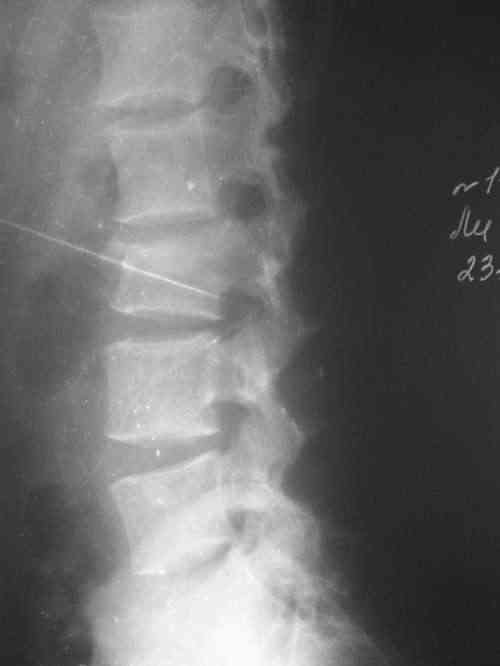

Принял по дежурству пациента с DS: Кататравма. Сочетанная травма. Закр. внутрисуставной оскольчатый перелом обеих пяточных костей (угол Белера 0-5 град.) Компрессионный неосложненный перелом тела L3 с клиновидной деформацией. Перелом левой седалищной кости без смещения с нарушением функции тазовых органов.

Подвесил его гамачок в положении по Волковичу (лечение в захолустных больничках сводится к реклинации и в надежде, что лигаментотаксис сделает свое дело). Не смотря на наличие "клина Урбана", движения и чувствительность в н/конечностях сохранены. Реклинация будет проводиться дозированно по конрольным снимкам. Моча выводится катетером. Гематурии нет. Планирую остеосинтез пяточных костей. Если диаспора достанет SFS Plates, то открыто. Если нет - аппаратная дистракция.